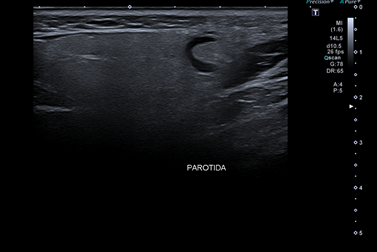

Hallazgos ecográficos

Se realiza ecografía clínica que muestra una imagen redondeada de márgenes regulares hipoecoica de 7,7 mm, sin tabicación y con refuerzo acústico posterior, que parece localizada en la glándula parótida derecha.

Señal doppler dudosa. Junto a esta lesión se visualiza otra de similares características, pero de menor tamaño.